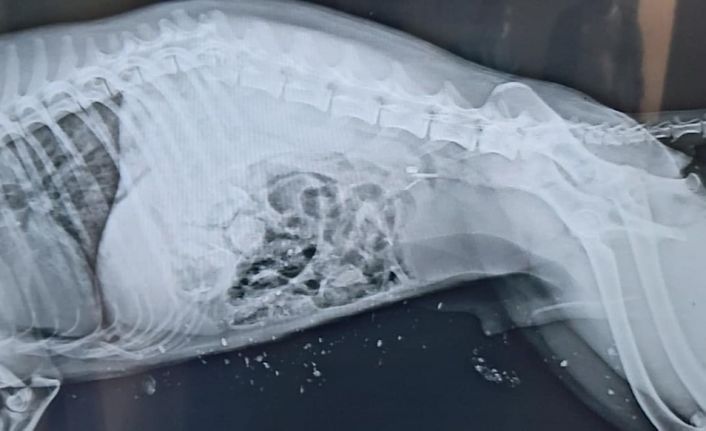

Edinilen bilgilere göre, Iğdır merkezde otoyol üzerinde bir aracın çarpması sonucu yaralanan Çakal’ı gören vatandaşlar ekiplere haber verdi. Haber verilmesi üzerine olay yerine gelen ekipler, ağır yaralı Çakal’a ilk müdahalesini yaparak hayvan barınağına götürdü. Daha sonra, Kafkas Üniversitesi Veteriner Fakültesi Hayvan Hastanesi Kliniğinde yapılan radyolojik muayenede, Çakal’ın omuriliğinin kırıldığı, ön bacaklarında parçalı kırık ve kanama olduğu, bu bulgulara bağlı olarak arka bacaklarının tutmadığı tespit edildi. Ağır yaralanan Çakal, Kafkas Üniversitesi Veterinerlik Fakültesi Hayvan Hastanesi’nde tedavi altına alındığı öğrenildi.